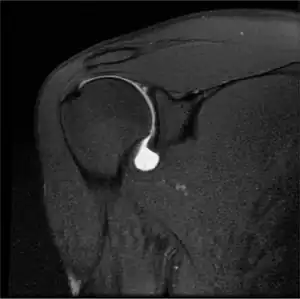

Twelve varieties of SLAP lesion have been described, with initial diagnosis by MRI or arthrography and confirmation by direct arthroscopy.[6]